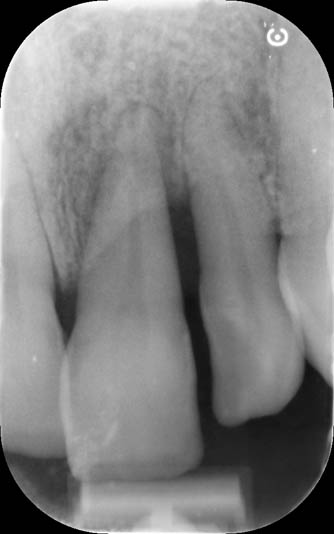

The rehabilitation of this periodontally compromised tooth required a multidisciplinary approach, combining both periodontal and orthodontic treatments.

Following an initial phase of non-surgical periodontal therapy aimed at removing subgingival calculus, Dr. Anna Mariniello performed both upper and lower alignment using a lingual, non-bracket orthodontic technique, employing active retainers applied to the lingual surfaces of the teeth.

At the end of the orthodontic treatment, a coronally advanced flap was performed according to the De Sanctis and Zucchelli technique, involving papilla preservation and connective tissue grafting, to restore the gingival contour and the papilla between teeth 21 and 22.